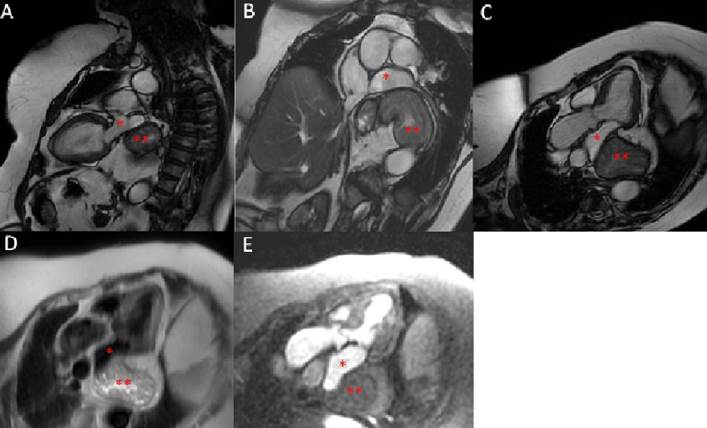

Paciente de sexo femenino de 67 años, con hábito pícnico (peso 90 kg, talla 150 cm) y antecedentes de hipertensión arterial en tratamiento con losartán 50 mg/día. Historia de meses de evolución de disnea de esfuerzo CF II sin causa clara. Historia de dispepsia y episodios de reflujo gastroesofágico. ECG en ritmo sinusal 78 cpm, QRS fino, sin alteraciones de la repolarización. Presentaba ecocardiogramas que eran similares desde hace tres años donde se informa una masa que comprime y/o desplaza la AI sin poder dilucidar con claridad su etiología, asociado a una mala ventana ultrasónica. Por esta razón es enviada por su médico tratante para realización de una RMC con el fin de esclarecer el diagnóstico. La resonancia informa ventrículo izquierdo con volúmenes de fin de diástole y fin de sístole normales, FEVI conservada y destaca la presencia de una masa extracardíaca en el sector posterior de la AI, que desplaza y comprime parcialmente a esta y la vena pulmonar inferior izquierda; por características morfológicas y caracterización tisular corresponde a estómago. En suma, gran hernia hiatal con desplazamiento y compresión parcial de AI y vena pulmonar inferior izquierda (figura 1).

Luego, con este planteo se realiza un nuevo ecocardiograma Doppler con el fin de contar con una técnica de mayor accesibilidad para un eventual seguimiento cardiovascular. En este se constata una regular ventana ultrasónica y se evidencia una masa retroauricular en íntimo contacto con la aurícula izquierda y sobre pared inferolateral del ventrículo izquierdo de difícil caracterización (figura 2A). Contando con la información de la resonancia se completa el estudio ecocardiográfico y se le pide a la paciente que ingiera una bebida carbonatada en decúbito supino (en este caso, agua con gas, a modo de “contraste”). Se visualiza el pasaje de las microburbujas al interior de la masa (en este caso, el estómago), lo que permite confirmar el diagnóstico ecocardiográfico de hernia hiatal (figura 2B). Dados estos hallazgos en los estudios de multimodalidad de imagen cardiovascular, es enviada por su médico tratante a valoración por equipo de gastroenterología y cirugía para definir directivas del tratamiento a seguir.